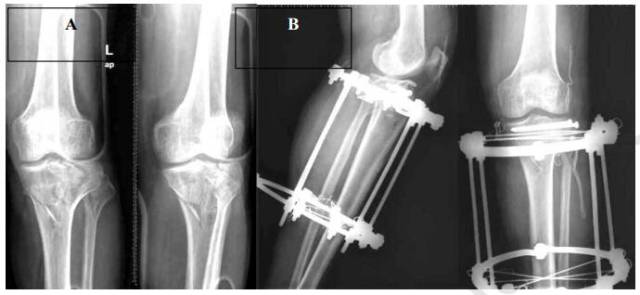

骨科外固定支架在复杂胫骨平台骨折的治疗中应用得越来越多,尤其是在软组织损伤或缺损较大、骨缺损或粉碎性骨折无法过度分离软组织和内固定的病例(图2)。外固定架允许患者在术后早期即可进行负重行走。组合式外固定架(Taylor空间支架和Ilizarov外固定架)可作为复杂胫骨平台骨折有效的终末固定方式,但是也存在针道感染和复位质量不佳等问题。此外,外固定架需要固定到骨折完全愈合,严重影响到患者的正常生活和舒适度。

Subasi等报道15例环形外固定架治疗的开放性胫骨平台粉碎性骨折,术后疗效可,但是骨折未能获得解剖复位,后壁粉碎性骨折在冠状面上复位丢失。为了解决上述问题,对于严重粉碎性骨折的病例,部分学者通过术中增加小切口复位复位后经皮螺钉固定或自体骨移植等方法,再使用组合式或环形外固定架固定。